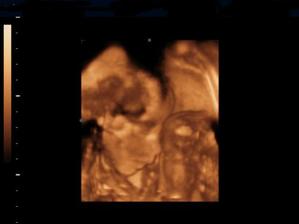

Naše kinderka

Dňa 24.8.2009 o 9.15 sa nám sekciou narodili naše krásne dvojičky Vanesska 2280 g a Larinka 2990 g. Robia nám veľkú radosť a moc ich ľúbime...